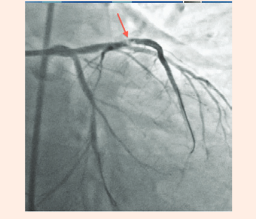

The patient was wheeled into the catch lab after pre-loading with 60mg Prasugrel and 300mg of Aspirin. He received 7,500units of unfractionated heparin and underwent coronary angiography from the right femoral route, which revealed 70% distal left main (LM) stenosis, and 70-80% ostial blocks of the left anterior descending (LAD) and left circumflex (LCX) arteries (Figures 2 & 3), (Video 1).The right coronary artery had a 50% stenosis at mid level (Figure 4). The patient was continuing to have chest pain despite prior administration of intra-venous morphine in the ER. He however was in a position to give informed consent for primary percutaneous intervention (PCI) subsequent to explaining that PCI would be a viable alternative keeping in view the urgency of intervention in his condition.

Figure 2 Coronary angiogram in right anterior oblique caudal view showing tight distal left main and ostial left anterior descending coronary arteries stenosis.